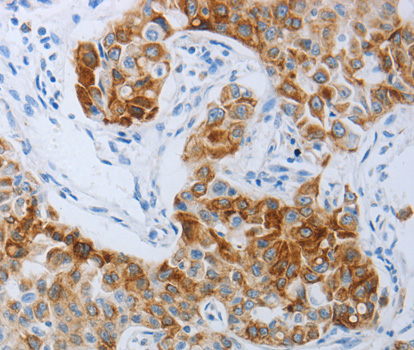

• A3059: image 2

Immunohistochemistry of paraffin-embedded Human lung cancer tissue using P2RY4 antibody.